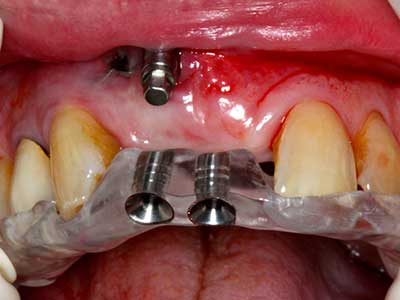

Bei der Knochenblockentnahme zeigen sich weitere Vorteile für die Piezochirurgie: Neben der bereits beschriebenen hohen Präzision bei der Osteotomie stellt sich gerade die Verwendung der dünnen Sägespitzen als besonders materialschonend heraus. Bei der Verwendung insbesondere von Lindemannfräsen sind mit deutlich höheren Entnahmeverlusten durch die dickere Instrumentenspitze zu rechnen (Lakshmiganthan, Gokulanathan et al. 2012). Die insbesondere bei retromolar entnommenen Blocktransplantaten notwendige basale Abtrennung wird durch speziell hierfür vorgesehene rechtwinklige Sägen erleichtert, so dass die Piezochirurgie als präzises, übersichtliches und sicheres Verfahren zur retromolaren Knochenblockgewinnung angesehen wird (Happe 2007) (Abb. 1-12).

Indikation: Bone Splitting

Knochengewebe ist nicht nur rein mineralisch, sondern auch in wesentlichen Anteilen aus Kollagenfasern aufgebaut. Dies gewährleistet neben einer guten Druckfestigkeit eine gewisse Flexibilität, welche für die Durchführung von Augmentationen genutzt werden kann. Bei der klassischen Expansionsplastik im Sinne eines Bone Splittings wird der atrophierte Kieferkamm in seiner Längsachse gespalten und nach Erreichen einer ausreichenden Osteotomietiefe vorsichtig aufgedehnt (Abb. 13-16), idealerweise ohne den Kiefer wesentlich zu deperiostieren (Brugnami, Caiazzo et al. 2014, Stricker, Fleiner et al. 2014). Bewährt haben sich Schrauben- und Plattensysteme mit zunehmender Expansionsdistanz, um die beiden Knochenlamellen unterhalb der Bruchschwelle voneinander zu distanzieren. In der Regel werden Restknochenbreiten von mindestens 3-4 mm gefordert (Chiapasco, Zaniboni et al. 2006), um eine ausreichende Flexibilität und knöcherne Bedeckung der einzubringenden Implantate zu gewährleisten. Ggf. kann eine ein- oder beidseitige vertikale Entlastungsosteotomie die Flexibilität verbessern. Als Alternative zur klassischen Technik wurde eine Kombination mit weiteren augmentativen Techniken vor allem auf der bukkalen Seite beschrieben.

Mittels Piezosägen erfolgt die Anlage des Splittings besonders schonend und ohne wesentliche Dimensionsverluste, so dass sich keine signifikanten Unterschiede von Implantaten im gesplitteten Kiefer im Vergleich zum nicht defizitären Alveolarkamm gezeigt haben (Chiapasco, Zaniboni et al. 2006, Danza, Guidi et al. 2009). Gerade beim lokal begrenzten und tiefen Splitting ist jedoch stets auf eine ausreichende Wasserkühlung zu achten, um thermische Belastungen in den apikalen Osteotomiebereichen zu vermeiden.